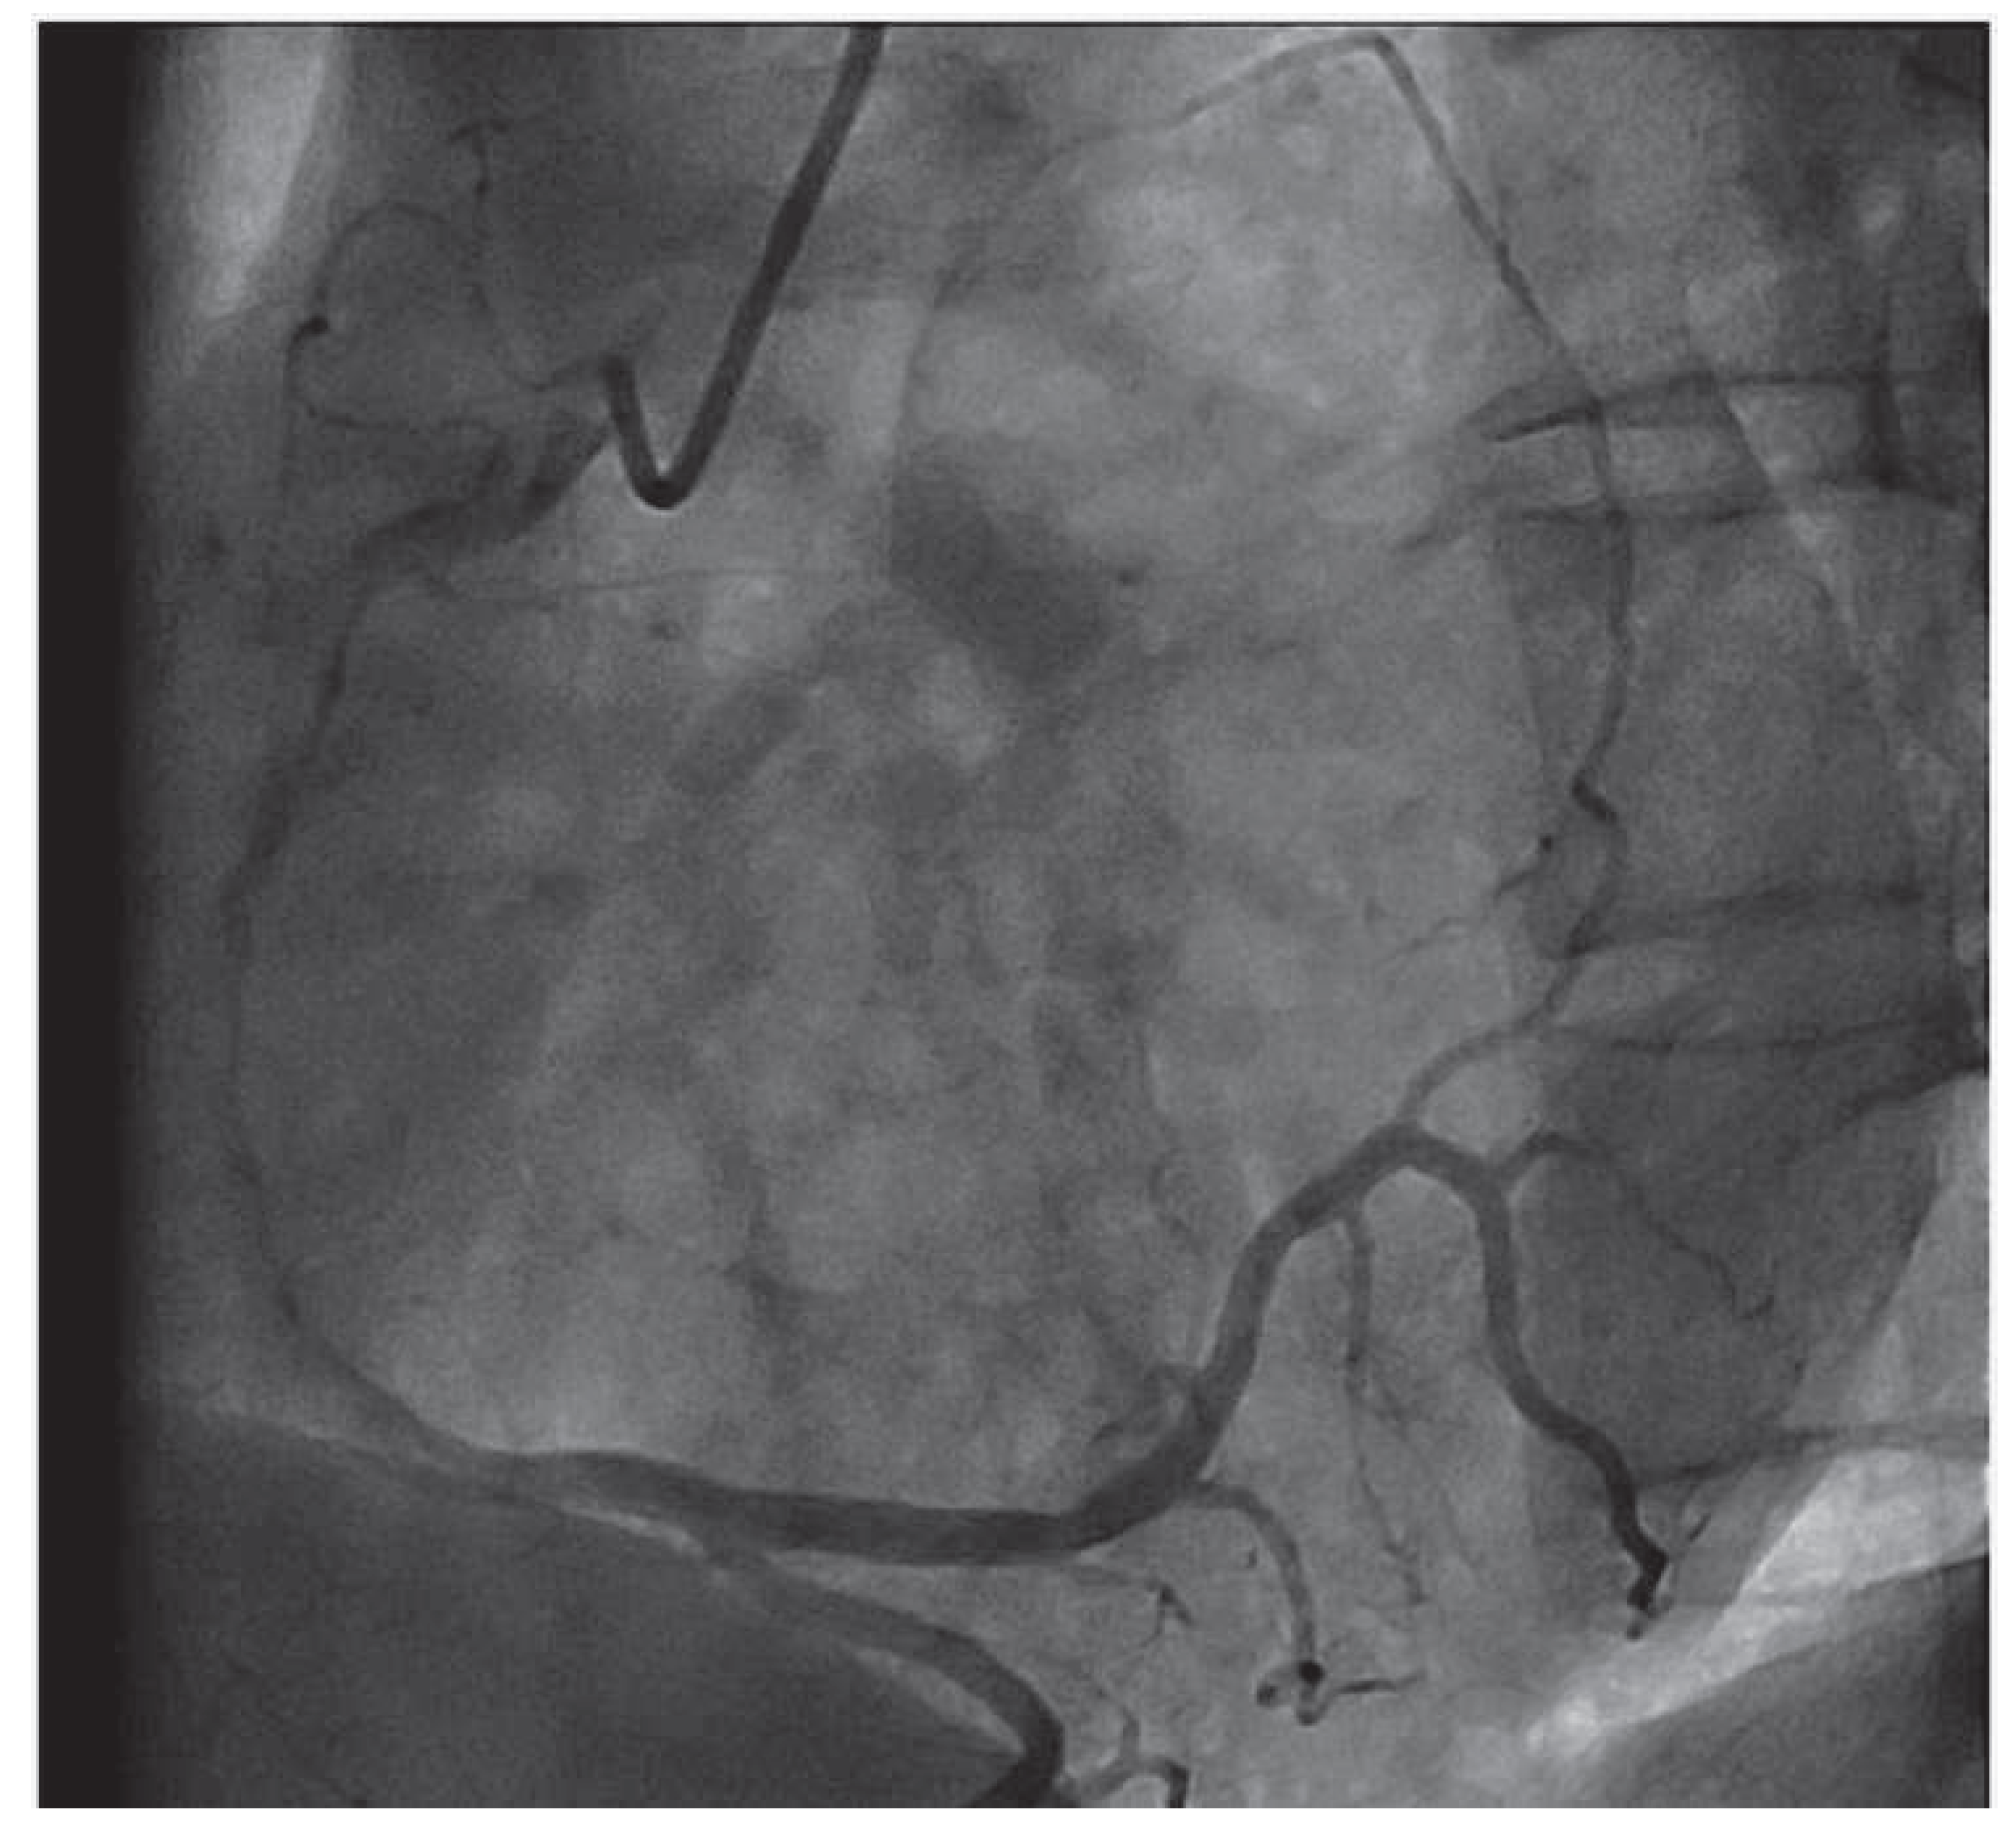

Valentine in the Heart

Case Report

- Gavaliatsis, I.P. “Right posterior” sinus node artery. Int J Cardiol. 2000, 75, 301–303. [Google Scholar] [CrossRef] [PubMed]